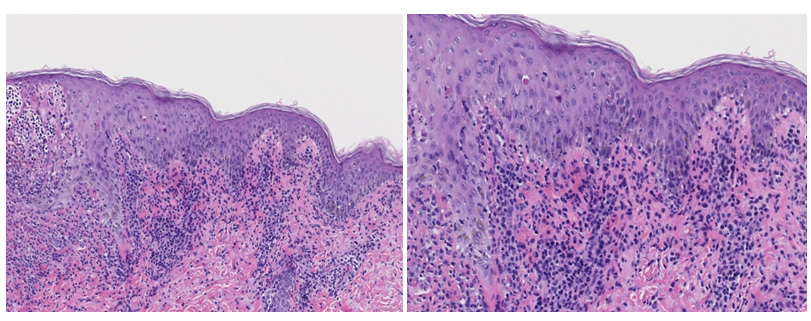

Skin examination revealed diffuse hemorrhagic vesiculopustules in different stages of healing involving the trunk, extremities, and face (Figure 1A)(Figure 1B). A skin punch biopsy from the right leg showed features of PLEVA with a lymphocytic infiltrate along the dermoepidermal junction, RBC extravasation, and epidermal necrotic keratinocytes. There was marked subepidermal edema with inflammatory cells and interface dermatitis, which extended down the hair follicle with intraepithelial apoptotic cells, but distinct herpetic viral cytopathy was not appreciated (Figure 2)(Figure 3). However, varicella-zoster virus (VZV) was detected by PCR from this skin site. The patient had elevated IgM titer to varicella, but no detected IgG antibodies to VZV. The patient was then diagnosed with primary varicella (chicken pox) and discharged on Valacyclovir 1gm TID for 7 days. At follow-up visit one-week later lesions were resolving.

Figure 3 E&F Higher power (10x & 20x) H&E section showing an inflammatory lymphoid infiltrate at the dermoepidermal junction, dyskeratotic cells, and erythrocyte extravasation.